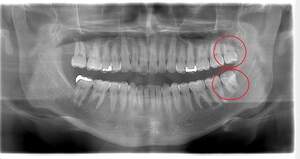

右下の親知らずが疼く症例

- 抜歯前写真(レントゲン)

- 抜去歯の写真(CT画像)

| 年齢 | 30代・女性 |

|---|---|

| 主訴 | 右下親知らずが疼く |

| 親知らずの生え方 | 横向きに生えている |

| 抜歯時間 | 40分 |

| 費用 | 約8,000円(保険診療、CT代含む) |

| 抜歯内容 | 右下の親知らずは横向きに生えて埋まっているため、麻酔をし親知らずの奥に切開を入れて歯ぐきを開き、歯を囲んでいる骨を削り歯の頭部分を割って出してから、残った根の部分を取り出して抜歯は終了しました。 歯ぐきを切った部分は糸で縫っています。このケースでは根の先端が神経に近く麻痺のリスクがありましたが事前にCTを撮影し、神経との位置関係を確認していたため、麻痺が残ることはありませんでした。 約1週間後に糸取りを行い、その際も多少の痛みや腫れはありましたが後日その痛みも無くなりました。 |